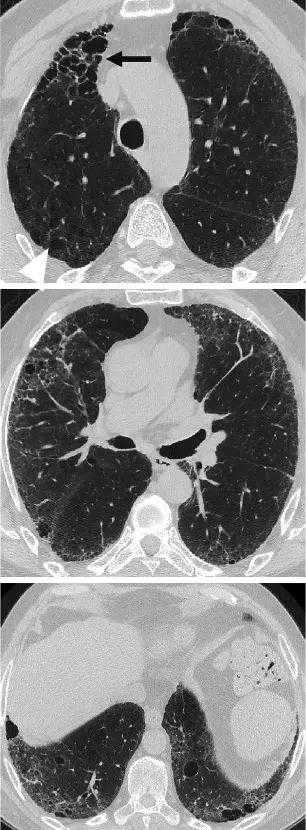

图6:HRCT显示混合性肺气肿和纤维化伴厚壁大囊肿(肺纤维化和肺气肿合并,厚壁大囊肿模式)。组织病理学显示主要与吸烟相关的间质纤维化。

图7:一名66岁男性吸烟者被诊断为特发性肺纤维化和肺气肿(CPFE,大的厚壁囊肿模式),病程4年。在左上角图像中,与肺气肿一致的无清晰可见壁的低密度病变(箭头)在隔膜附近可见,位于肺纤维化区域内。在接下来的4年里,随着纤维化的成熟,低密度病变合并并扩大(箭头),形成厚壁的囊性病变。

图8:69岁男性特发性肺纤维化,HRCT显示双肺弥漫性肺气肿和下肺明显纤维化(CPFE,无法分类模式)。右上肺肺气肿是混合性肺气肿(黑色箭头)和孤立性肺气肿(白色箭头)的组合。中间可见混合性肺气肿,下部可见混合性和孤立性的肺气肿和小叶中央肺气肿。